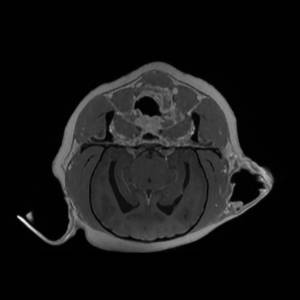

Main Gallery

Playing with a photo gallery function. It is possible to have multiple galleries, each within a namespace.